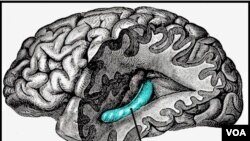

Hippocampus, blok merah di bagian lain otak yang berperan dalam ingatan, juga bisa terganggu akibat stroke.

"Ketika kita tahu ingatan seseorang berkurang seiring bertambahnya usia, kita biasanya mengaitkan perubahan itu dengan perubahan fungsional atau perubahan struktural dalam hippocampus. Yang kita temukan pada stroke ringan adalah kehadiran stroke di otak juga terkait fungsi daya ingat."